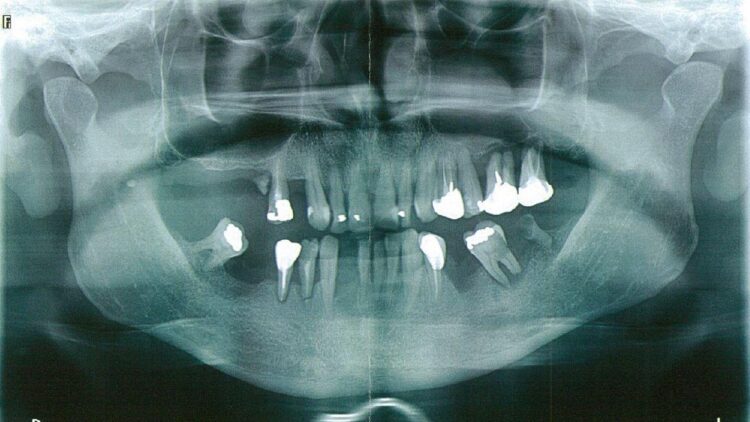

Entre la fin des années 1990 et le début des années 2000, Marseille a été secouée par une série d’actes violents rituels portant sur des mutilations dentaires. Ces pratiques, principalement ciblées sur des enfants issus de familles originaires d’Afrique subsaharienne, ont révélé l’importation clandestine de rites ancestraux en marge du cadre légal français. L’affaire a pris une ampleur judiciaire considérable après qu’une enquête approfondie ait permis d’identifier plusieurs suspects clés, parmi lesquels figuraient Lionel et Jean-Claude Guedj, accusés d’avoir organisé ou couvert ces actes.

- Une expertise médicale confirmant les traces irréfutables de violences dentaires ;